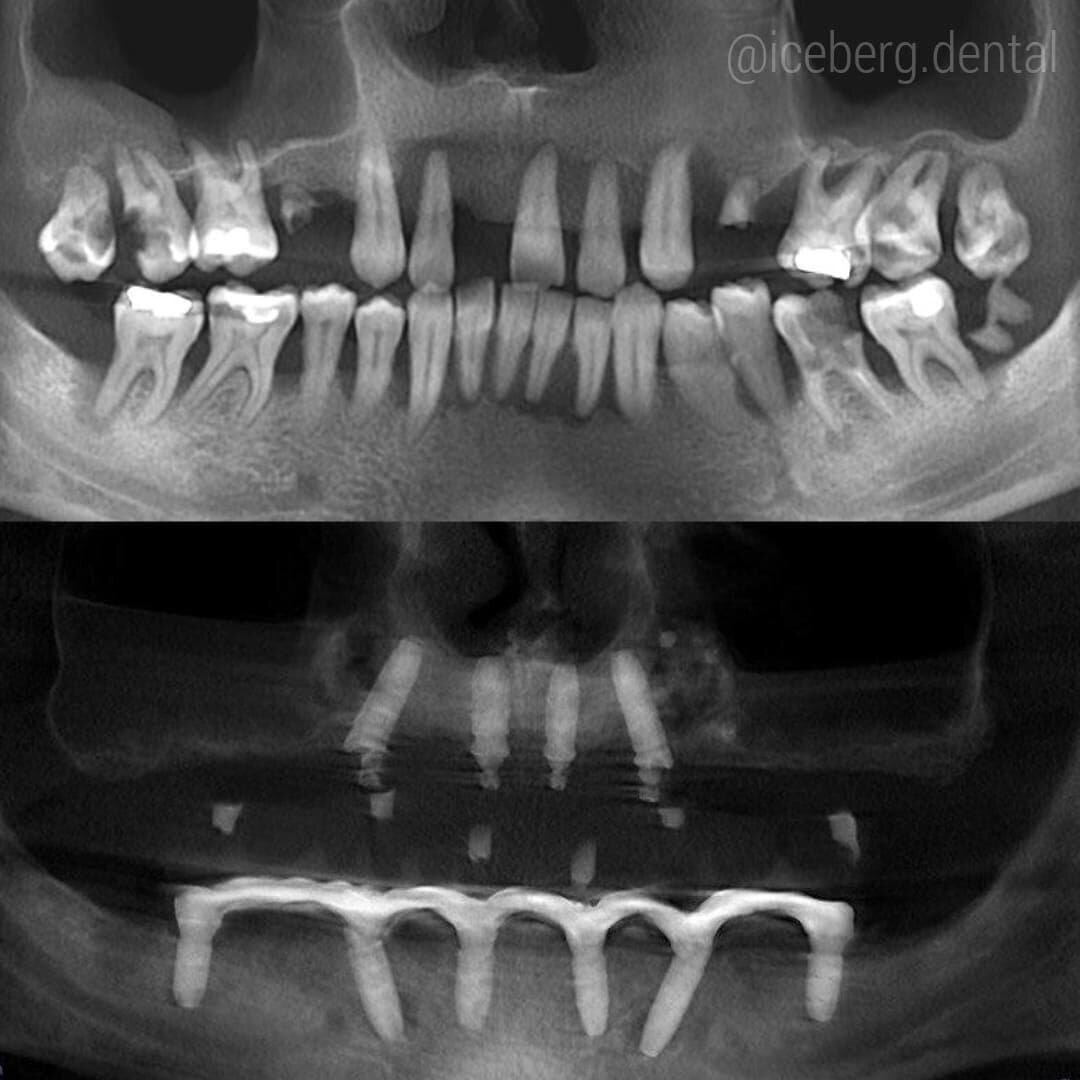

Причина столь кардинального подхода - пародонтит.

Кость разрушена до верхушек корней и спасение зубов было невозможно - смотрим на снимок.

Это промежуточная работа по технологии 🌟All on four🌟

Что дословно - «всё на четырёх».